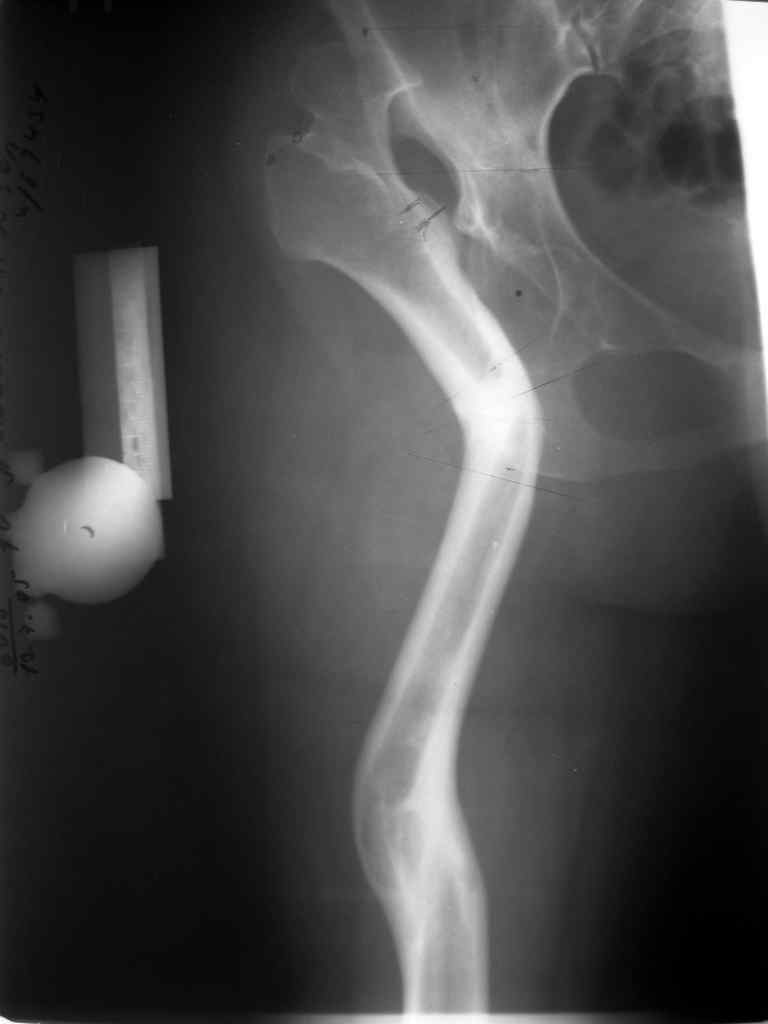

Поднят очень интересный вопрос об эффективности создания опорного бедра по Илизарову у молодых пациентов (ок). Наверное мне не повезло и я не

видел положительных результатов после этих операций, а вот проблемных больных приходится видеть достаточно часто. Причем сроки их обращения

после остеотомии короткие - 3-5 лет, а выполнение эндопротезирования после остеотомии на двух уровнях с многоплоскостной деформацией является

серьезным испытанием и для пациента и для хирурга. Я тоже не сторонник эндопротезирования в молодом возрасте, но уж после неудачных остеотомий

остеотомии. Я представил Р-граммы больных с неудачными р-ми после остеотомий.

Эндопротезирование у них было на порядок сложнее в отличие от артропластики без проведения остеотомии.